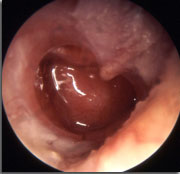

Parmi les enfants qui ont développé une otite (22 %), il existait une inflammation du tympan sans liquide dans 7 % des cas. Le tympan n’était pas bombant pour 19 % des cas, modérément bombant (45 %) ou franchement bombant (29 %) ou perforé (6 %). En cas d’otite bilatérale, l’inflammation était asymétrique dans 54 % des cas. L’âge médian au diagnostic était de 16 mois (6 à 35) et le nombre d’otites par enfant a varié de 1 à 10. Sur les 28 cas d’otites bénignes non traitées, 4 ont évolué vers une otite franche.

Au total, les aspects de l’otite sont très variés même chez un seul enfant en cas d’atteinte bilatérale. Des modifications otoscopiques sont observées dès le premier jour de la rhinopharyngite. L’utilisation de scores est indispensable pour établir les critères d’un traitement antibiotique.